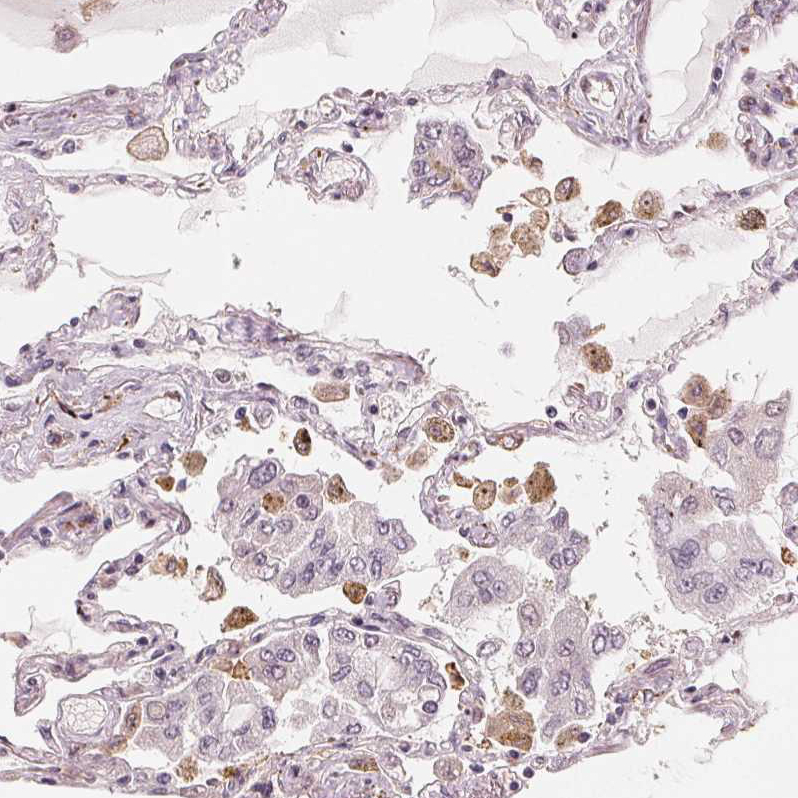

Immunohistochemical staining of human lung shows strong cytoplasmic positivity in macrophages.